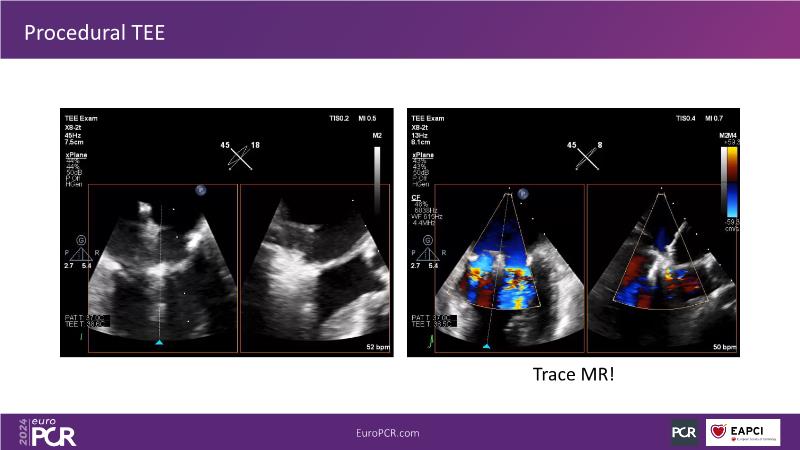

Watch this session to gain insights into the clinical evidence of mitral TEER therapy for the Asian population, learn techniques for implanting a MitraClip in patients with challenging anatomy, and understand how to use the four clip sizes for optimal outcomes. The session also covers educational aspects of clipping in dextrocardia, the benefits of reserve bending of the transseptal needle for tenting and puncture, new steering maneuvers for dextrocardia patients, and the importance of understanding anatomy and collaborating closely with the echo team for success.